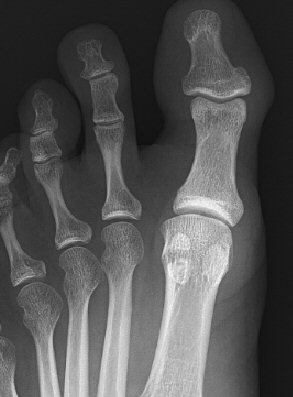

Kan vara svår att skilja från normalvariant med bipartit sesamben, frakturlinje är ofta rakare än vid än bipartit sesamben och vassare kanter vid fraktur.

Fraktur på mediala sesambenet, första två bilderna efter en månad, tredje bilden efter 5 månader